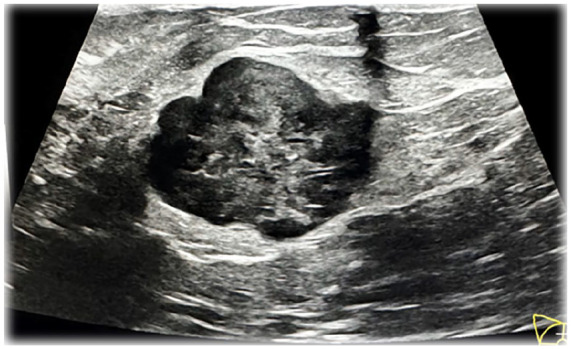

Metastatic melanoma to the breast is a rare phenomenon often mistaken for primary breast cancer due to overlapping clinical and imaging characteristics. We report the case of a 51-year-old woman with a history of melanoma resected 7 years earlier, presenting with severe left hip pain and a 6-month history of a right breast lump. Imaging revealed extensive metastatic disease, including lesions in the femoral head, breast, lung, adrenal gland, and thoracic spine. Pathologic examination of the hip lesion obtained during total arthroplasty, as well as biopsies of the breast and lung, confirmed metastatic melanoma. Histology revealed pleomorphic tumor cells with necrosis, while immunohistochemical analysis demonstrated SOX10 and S100 positivity, confirming the diagnosis. Genetic testing identified microsatellite stability with a tumor mutational burden of 16 mutations per mega base. This case shows the importance of thorough cancer histories and the use of immunohistochemical staining to distinguish metastatic melanoma from primary breast malignancies. Despite timely diagnosis and intervention, the patient's condition deteriorated rapidly, reflecting the aggressive nature of metastatic melanoma. This case highlights the need for vigilance in patients with a history of melanoma presenting with new breast masses to ensure accurate diagnosis and appropriate management.